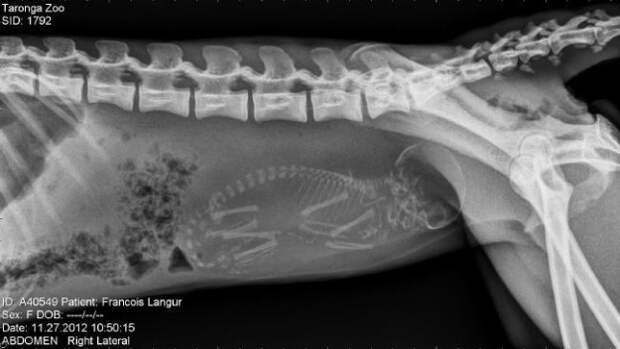

Вы когда-нибудь задавались вопросом, что происходит в утробе беременной кошки или собаки? Как там умещаются все эти крохотные детеныши и умудряются развиваться на протяжении всего срока беременности? Большинство беременных животных обследуют при помощи рентгеновских снимков. И это, надо отметить, очень любопытные снимки.